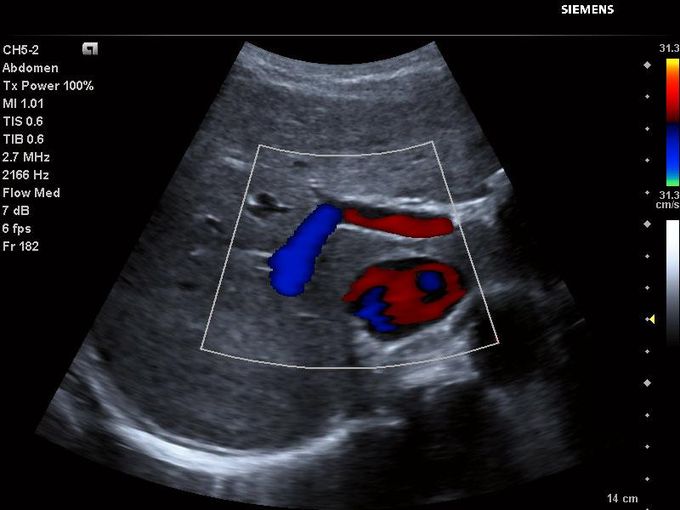

Кроме новой техники, можно заказать восстановленные медицинские системы: ультразвуковые сканеры, томографы, флюороскопы, ангиографы и хирургические установки С-дуга.